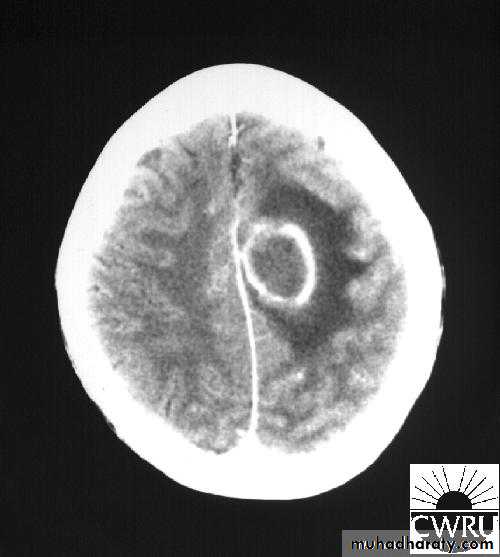

Brain Abscess CT with contrast

• CT Brain is performed with and without contrast.

• They will show a single (or multiple) space occupying lesion that is well delineated with an enhancing wall, with variable surrounding oedema.

Stereotactic Aspiration of Brain Abscess